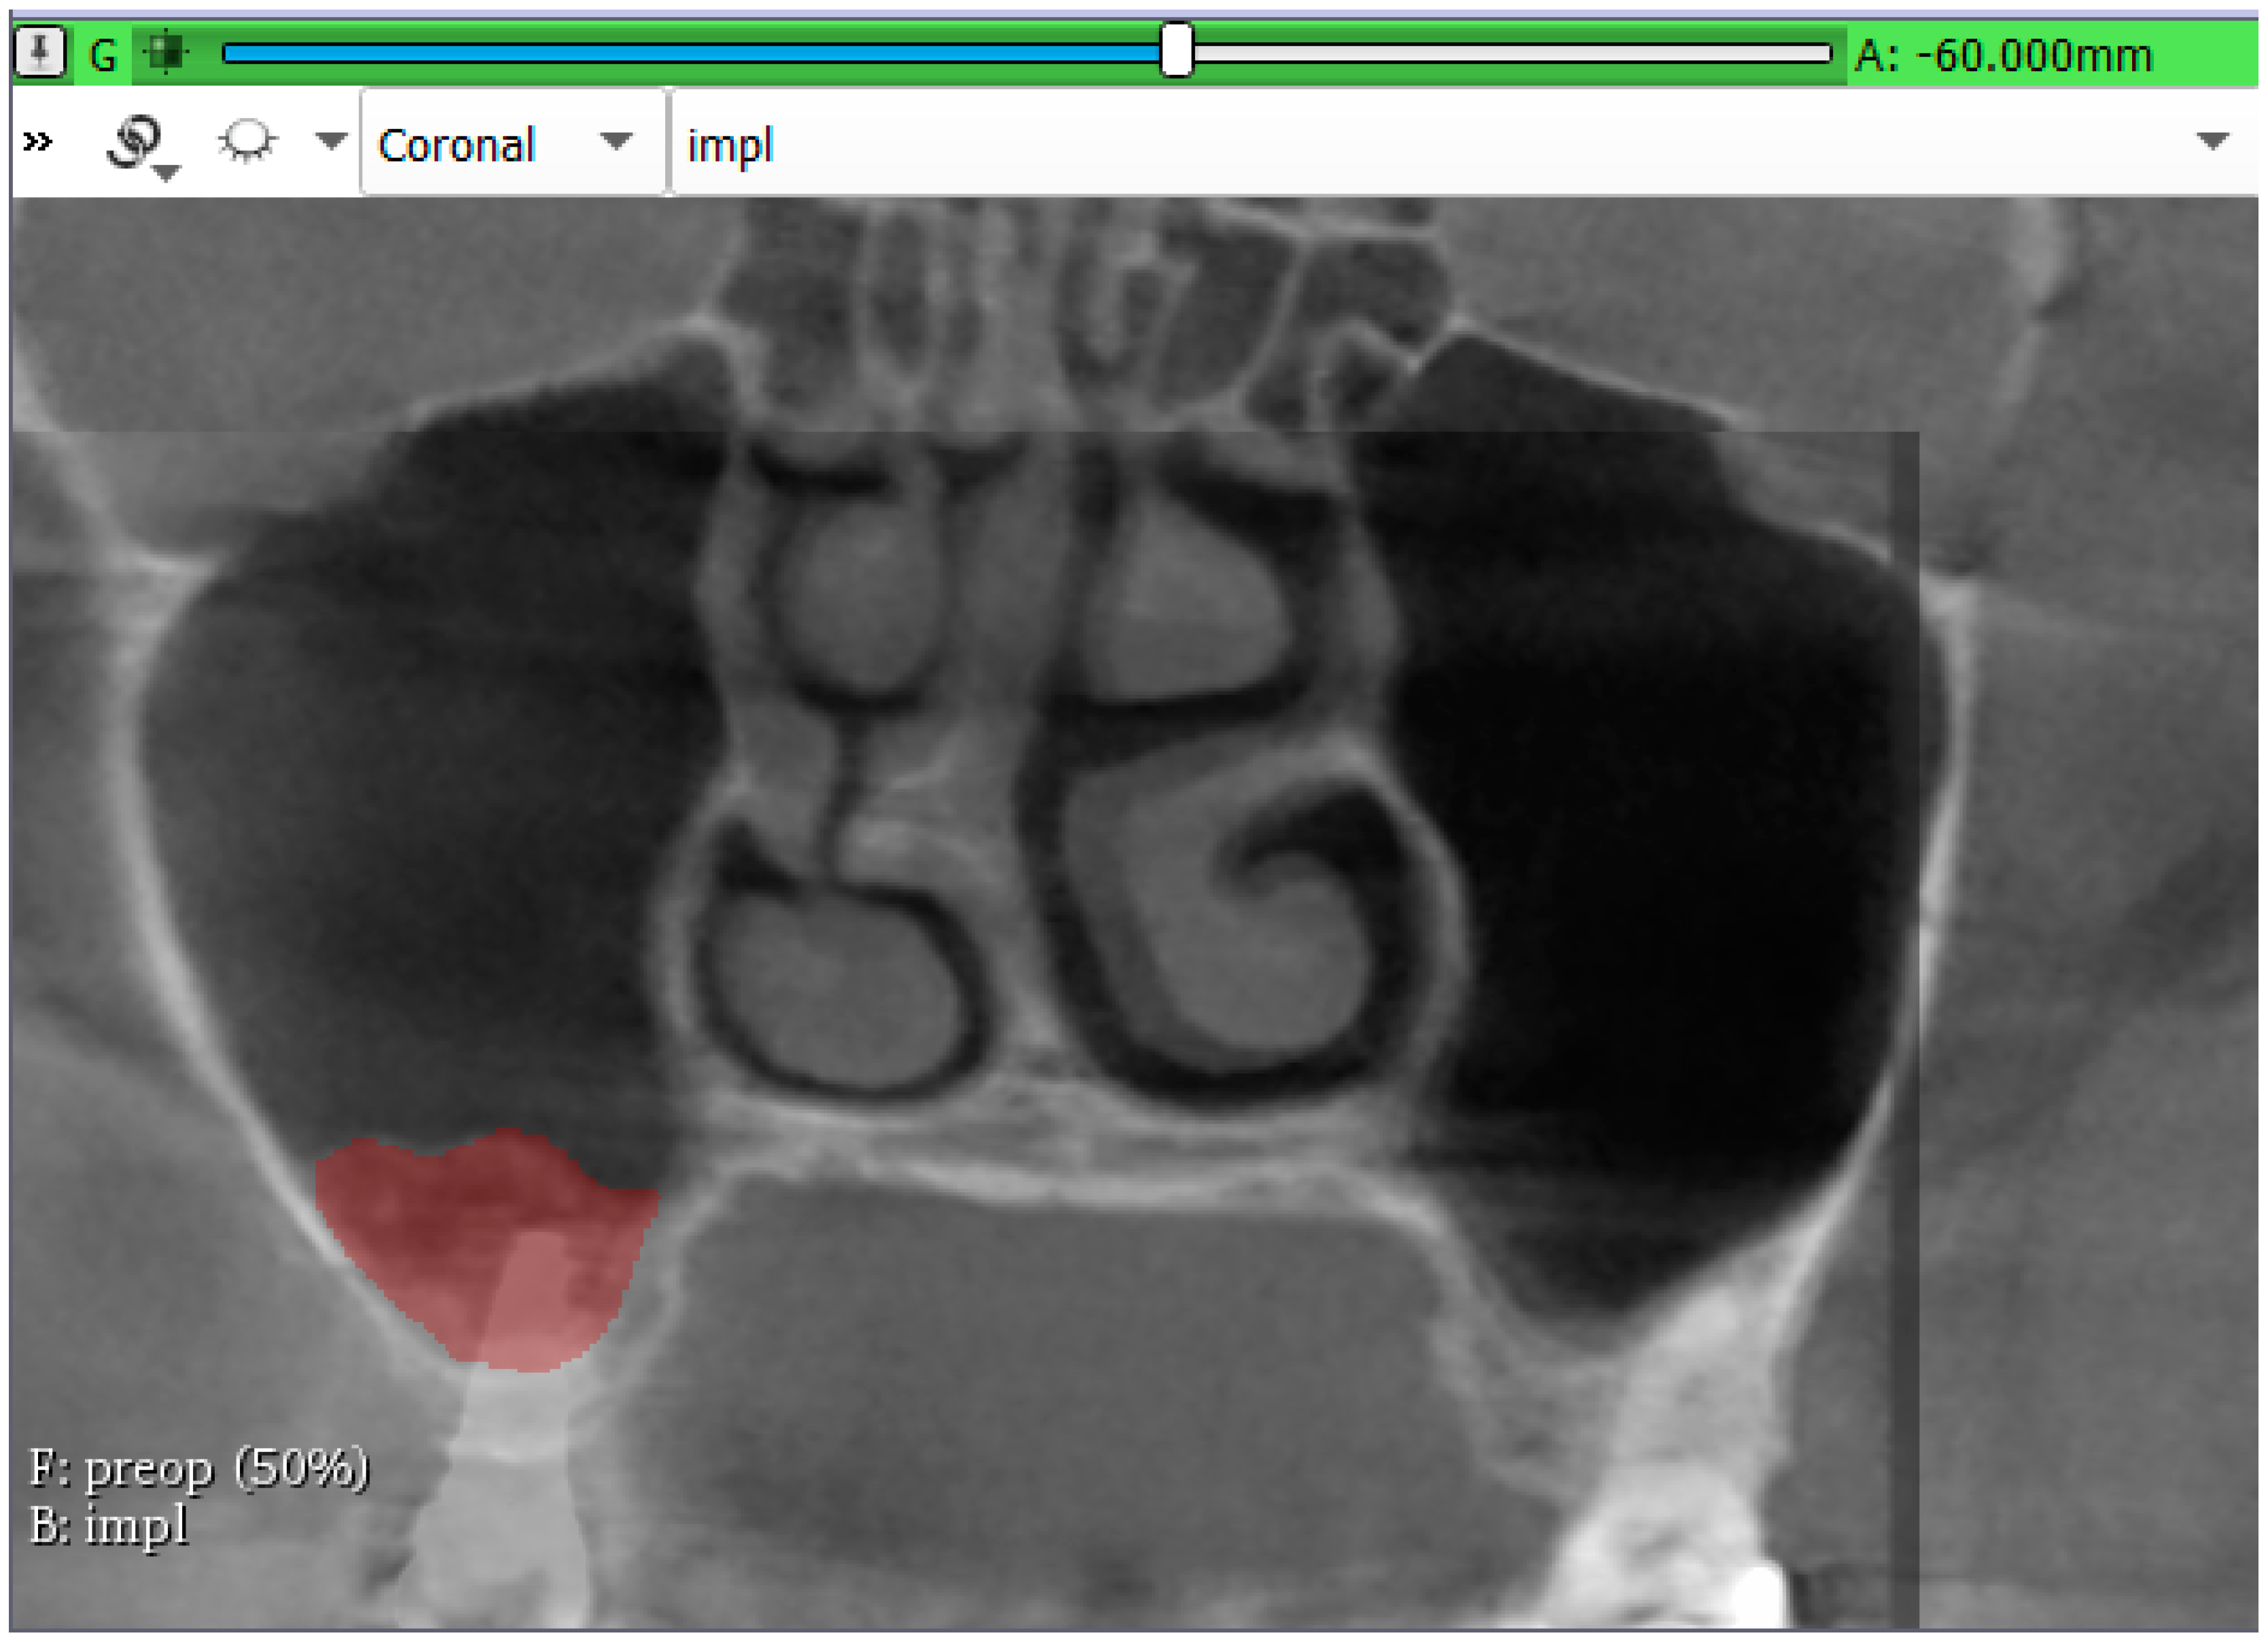

3.2. Volumetric Assessment of the Augmented Sinuses